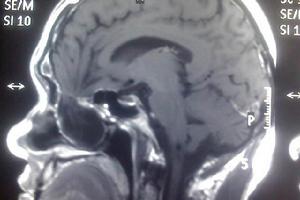

1.CT不僅可顯示顱骨缺損的形態,亦能顯示膨出的軟組織中是否含有腦脊液或腦組織,如合併腦膜腦膨出則可見與腦同樣密度的表現,可見腦室的大小、移位、變形等。對顱頂前半部腦膨出者,CT檢查,特別是套用三維重建技術,對於決定是否需要顱面重建以及選擇重建方法很有幫助,對顱底腦膨出者,冠狀CT掃描顯示更好。

2.磁共振(MRI)可見到顱骨缺損及由此膨出的腦脊液、腦組織、腦血管及硬腦膜組織信號的腫物。對顱骨缺損的分辨不如CT清晰,但對膨出的內容物解析度較高。